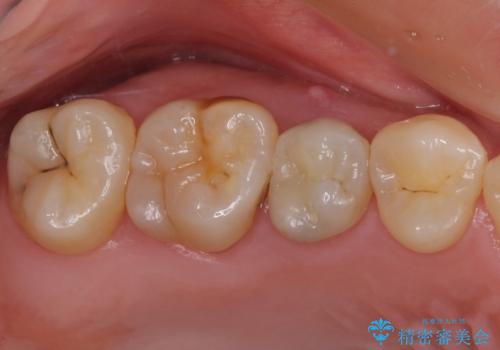

【根管治療】噛んだ時にしみる。最近になってズキズキ痛み、長引く痛みがある

担当医 河口智英